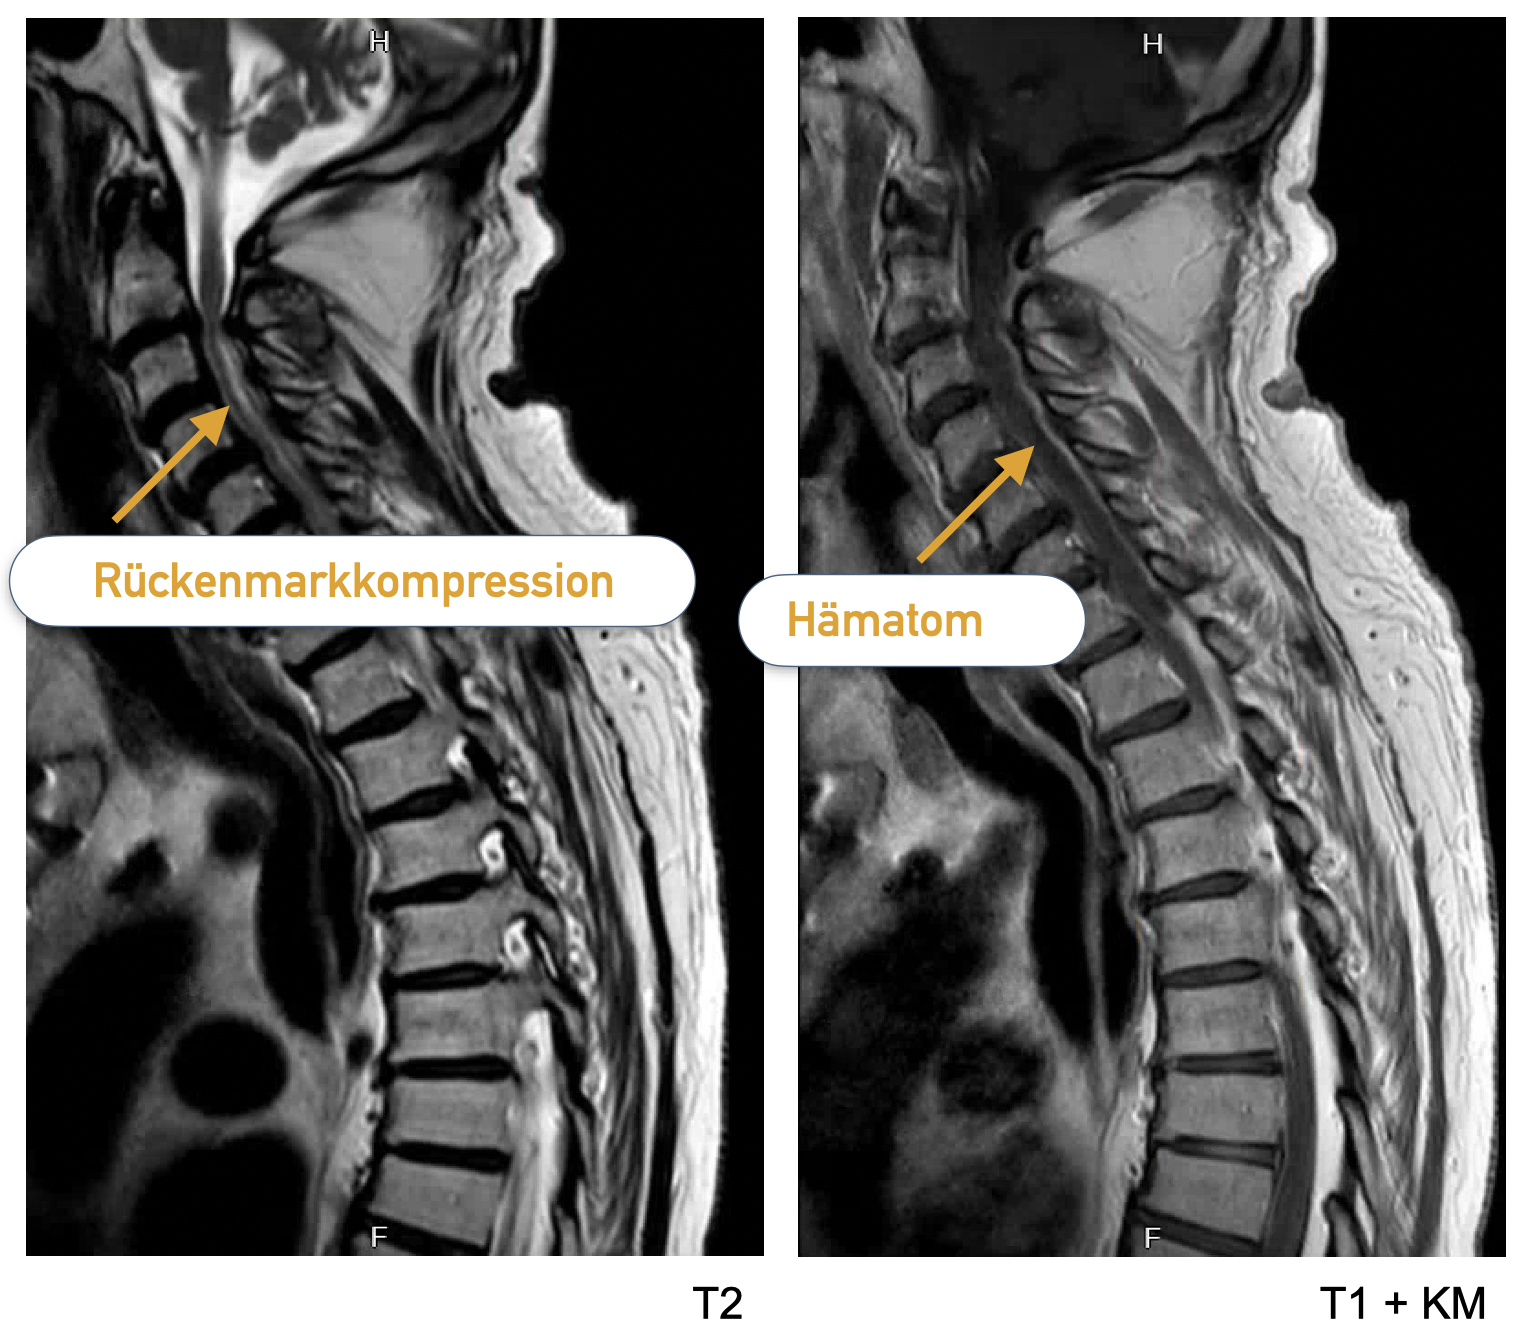

Patient 1 (spinaler Notfall)

Ein über 85-jähriger Patient verspürt nachts reißende Schmerzen zwischen den Schulterblättern, entwickelt rasch eine hochgradige Querschnittslähmung. Er nimmt eine orale Antikoagulation (OAK) mit Rivaroxaban (Xarelto) ein.

In einer Notfall-MRT zeigt sich ein intraspinales extramedulläres (im Rückenmarkkanal, entlang des Rückenmarks) Hämatom mit Kompression des Rückenmarks.